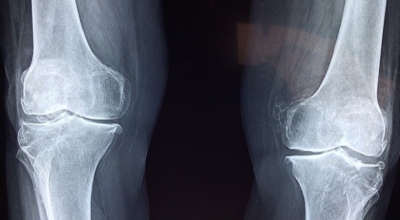

msm의 효능 - 관절 건강

뼈를 강화시켜주며 관절염에 많은 도움이 되어요. 관절의 활막과 연골 부분을 재구성하는 물질이 있어서 운동선수, 헬스를 취미로 하시는 분들, 등산하시는 분들이 복용하면 좋은 효과가 있다고 하죠. 또 관절염, 근육의 통증, 두통, 생리통에 효과가 있습니다.

황은 인체의 핵심 항산화 효소인 글루타티온의 합성에 기여하기 때문에 면역 체계를 강화시켜주며 염증과 통증에 대한 개선 효과가 생길 수 있답니다. 또한 황이 관절의 구성 물질로서 활용되는 재료이기 때문에 다이렉트로 관절의 건강을 지원할 수 있습니다. 실제로 관절염 환자들의 경우 황 수치가 낮은 특징을 보입니다. 미국은 msm을 섭취하는 사람들이 백만 명 이상일 정도로 인기 보조제라고 해요.

msm의 효능 - 만성염증, 통증, 항염효과

항염효과로 만성 염증, 통증 개선에 주요한 역할을 해요. 만성 염증 중에서도 골관절염이나 관절 통증을 억제하는 역할이 크기 때문에 관절 영양제에도 많이 활용돼요. 위염, 위궤양같은 점막 훼손을 회복시키는데도 효과가 있다고 하네요. 염증으로 인한 알레르기 증상 완화에도 보탬이 돼요.